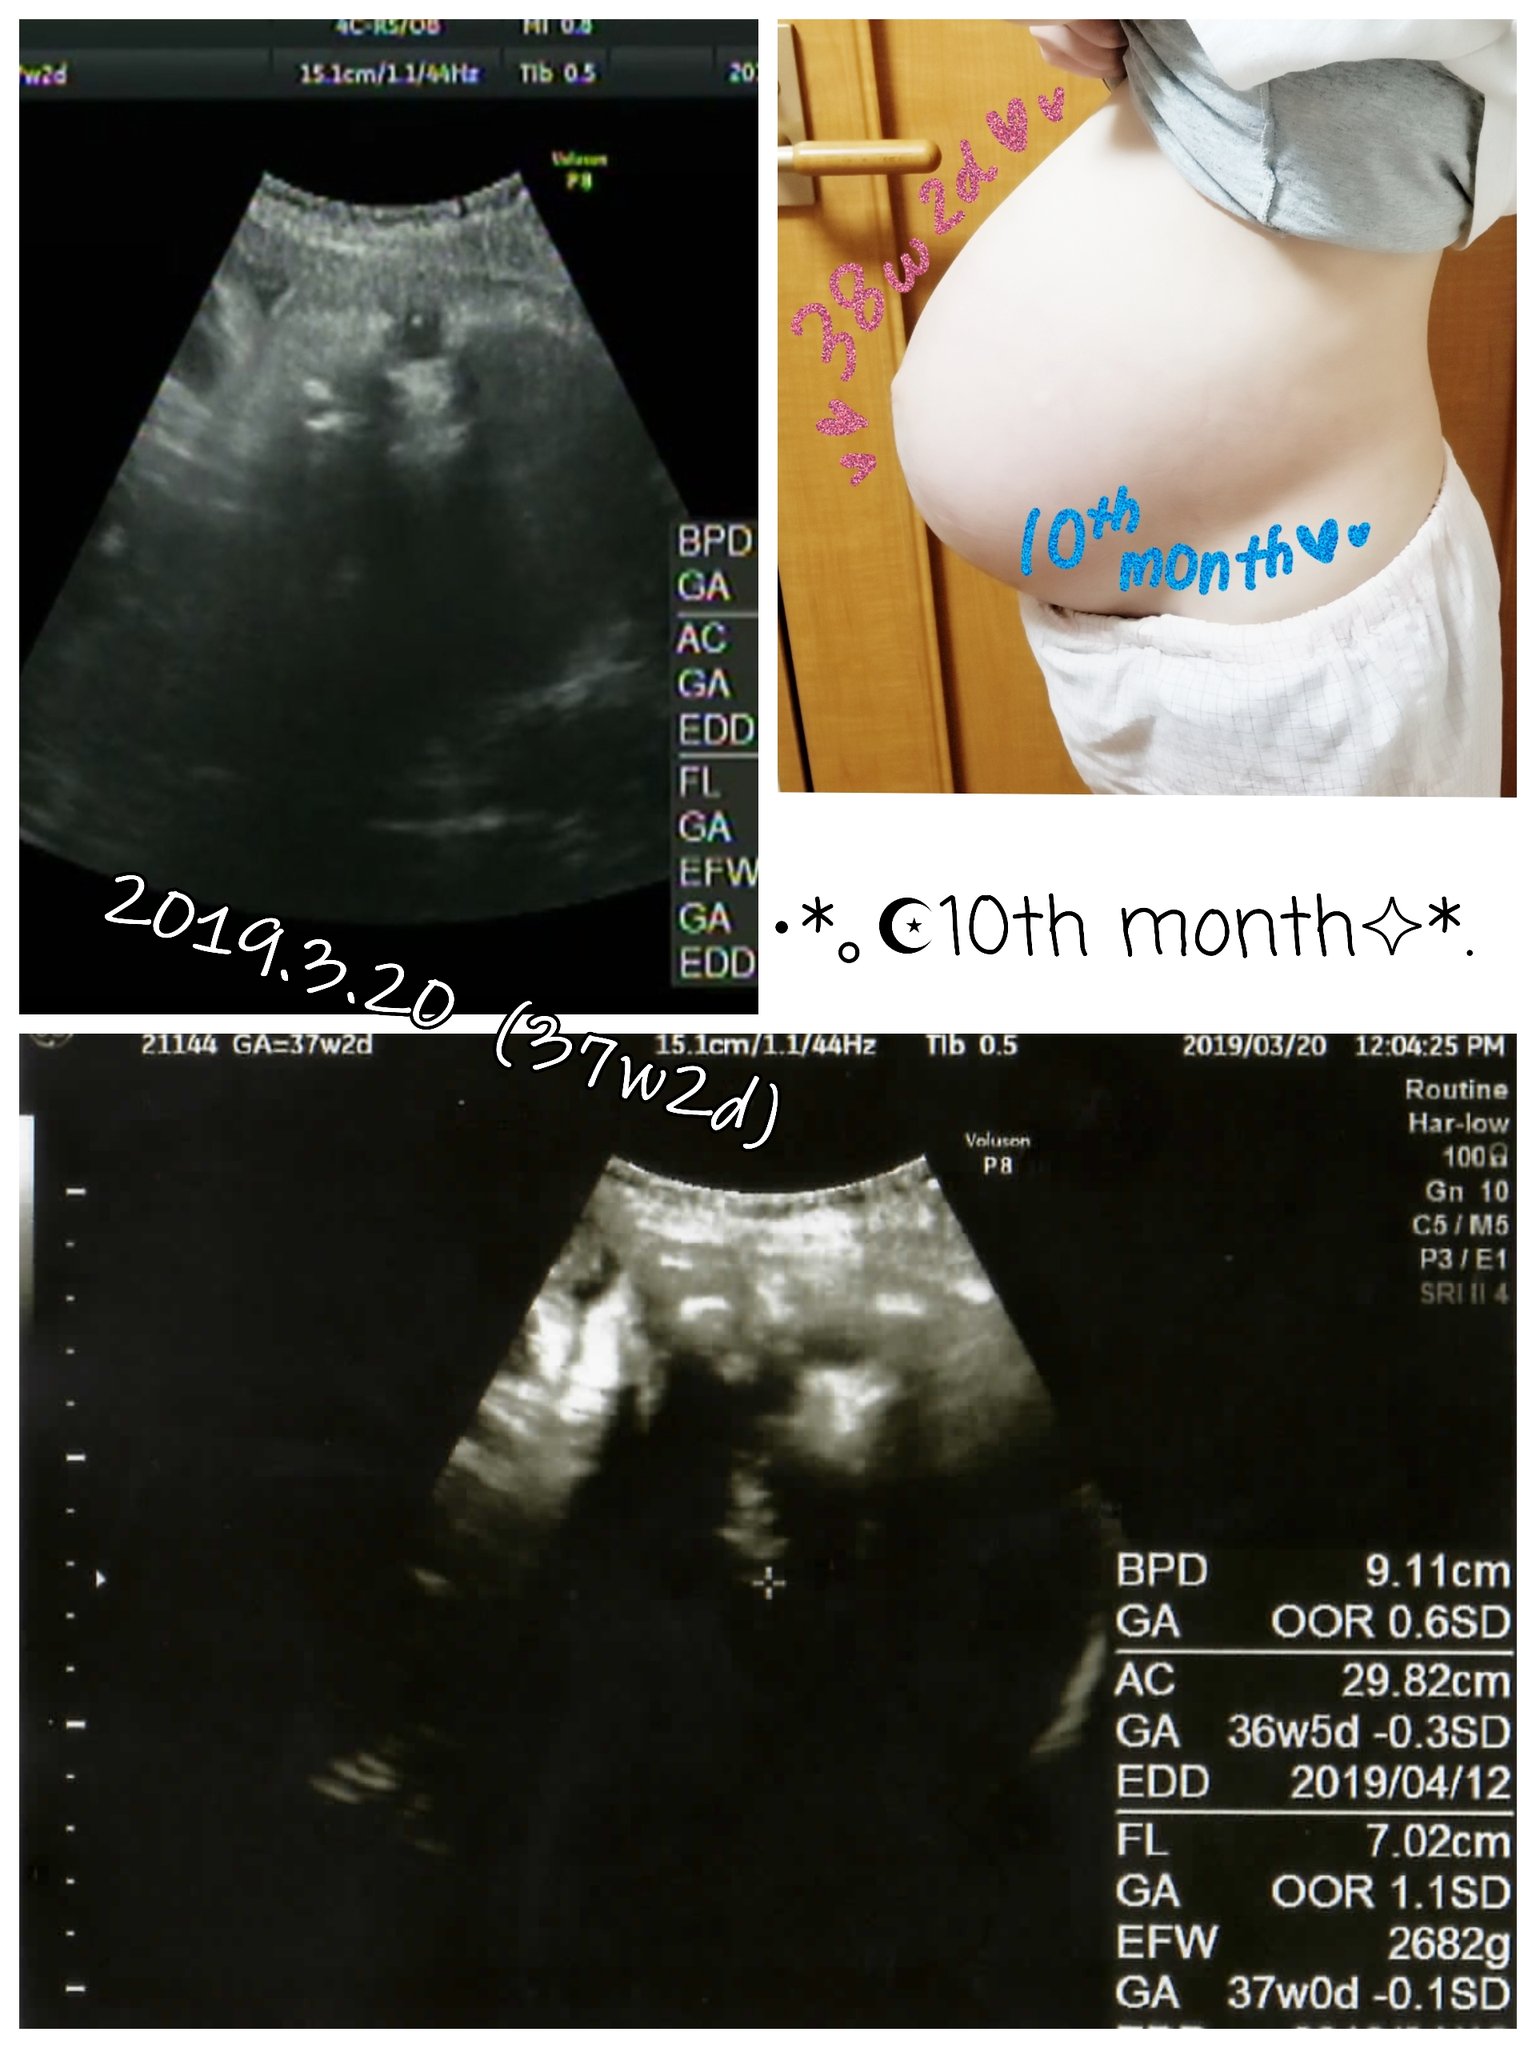

逆子 エコー 写真-妊娠10ヶ月(36週~39週目)のお腹の大きさ&体重&エコー写真 妊娠36週6日目、明日から正産期に入ります。 またまた久々の更新です。 義父の四十九日の法要も済ませ、今週末の納骨 9週の双子エコー写真2人同時にうつせた最後の日 12週〜17週の双子エコー写真どっちがどっちか分からない時期 18週の双子エコー写真性別と位置、大きさがはっきりしてくる時期 22週の双子エコー写真双子の逆子が常になった時期

ママにエールさんの妊娠36週目のエコー写真 2度“逆子”になった胎児はもう小学生! 子どもと共に読み返した当時の日記&エコー画像 赤ちゃんの心臓は元気に鼓動し、推定体重も2762gと順調。 ただ、「おりもの検査」を受けた際に、子宮口が指2本 とりあえず、エコー写真載せときます。今回のエコー写真はちょっとわかりづらいんですが。。。 妊娠29週目の4Dエコー写真 胎児(赤ちゃん)の大きさ(推定体重):1234g(28w3d相当) 私の体重もあまり増えなかったせいか?